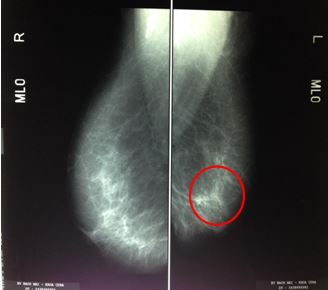

Trên phim chụp X- quang tuyến vú (mammography) cho thấy: vị trí ¼ trên ngoài vú trái có đám vi vôi hóa có tính chất ác tính (BIRADS 5). Vôi hóa lành tính vú phải.

Hình 1. Hình ảnh vi vôi hóa vị trí ¼ trên ngoài vú trái (vòng tròn đỏ)trên phim chụp X quang tuyến vú